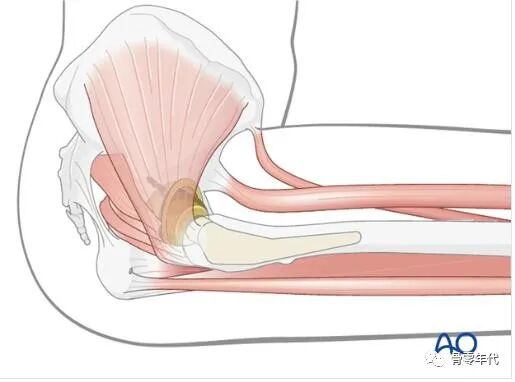

3.臀大肌和阔筋膜张肌准备

在外侧入路中,阔筋膜已经纵向切开。在阔筋膜前部做一个微斜切口(长度约为3-4厘米),该切口距离远到足以提供足够的长度,使组织滑脱到达股外侧肌筋膜(A)。然后,通过阔筋膜的前部切开延伸到阔筋膜张肌肌腹的近端和前部,大约70%的肌肉用于转移(B)。要转移的阔筋膜张肌的粘连部分通过手指来进行钝性松解。

类似的方法用于制备臀大肌。在阔筋膜的后部,在足够远的位置做一个轻微的斜切口(长度约为3-4厘米),以提供足够的长度,使组织滑脱到达股外侧肌的筋膜(c)。然后,通过阔筋膜的后切口向近侧和后侧延伸至臀大肌肌腹,以便将这块肌肉的大约30%用于转移(D)。将要转移的臀大肌部分通钝性分离,通过手指解剖释放粘连。

4.转移阔筋膜张肌

阔筋膜张肌远端转移到股外侧肌,同时在适当的张力下用多个中断的不可吸收的8字形缝合线固定。或者(没有在图中显示),如果不能动员外展肌进行直接修复,可以使用第1步中描述的骨隧道来固定阔筋膜张肌滑移。

5.转移臀大肌

将臀大肌移位于的阔筋膜张肌上方前方,远端用多次间断的不可吸收的八字缝线与阔筋膜张肌、股外侧肌缝合。阔筋膜远端解剖闭合,皮下组织和皮肤分层闭合。